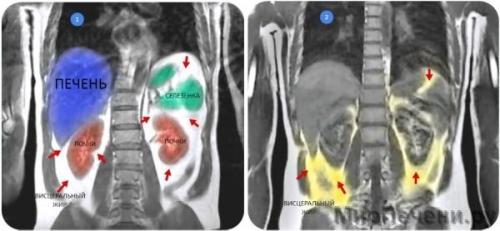

Внутреннее ожирение – состояние, при котором висцеральный, также известный как «активный» жир, влияющий на функционирование гормонов в организме, накапливается в брюшной полости человека, и его избыток чреват потенциально опасными последствиями уже лишь потому, что накапливается в брюшной полости – рядом со многими жизненно важными органами, такими как поджелудочная железа, печень и кишечник; чем выше его количество накапливается у человека, тем больше риск для определенных осложнений здоровья, таких как диабет 2 типа и сердечные заболевания.

Единственный способ наверняка подтвердить указывающие на ожирение внутренних органов признаки – это компьютерная томография (КТ) или магнитно-резонансная томография (МРТ), причем обе процедуры являются дорогостоящими и трудоемкими. Вместо этого доктора обычно используют общие рекомендации для оценки висцерального жира и потенциальных рисков для здоровья пациентов. Например, считается, что около 10% всей жировой ткани в организме занимает висцеральный жир: если подсчитать общее количество жира, а затем взять 10% от него, то сможете оценить, какое количество приходится на внутренние органы.

Висцеральным ожирением страдают даже внешне худощавые люди. При нерациональном питании нарушается обмен веществ, и жир начинает откладываться во внутренних органах. При этом висцеральное ожирение у мужчин и женщин можно диагностировать лишь при ультразвуковых методах исследования.